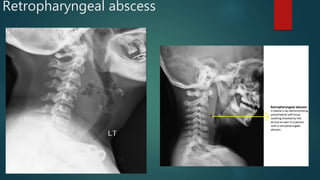

Retropharyngeal abscess

• #128 Annotations showing the normal width of the pre-vertebral soft tissue at the various cervical levels. The annotated pathological images reveals the magnitude of the soft tissue widening.

• #129 Huge fluid-gas filled rim enhancing abscess in the retropharyngeal space. Its extends over nearly the whole length of the cervical spine.